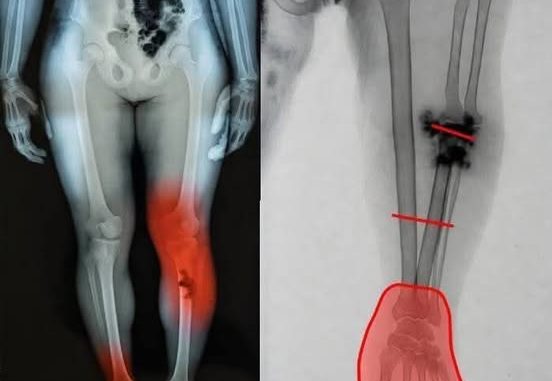

Medical research has identified a small number of myocarditis cases—an inflammation of the heart muscle—following certain mRNA vaccines, particularly among adolescent and young adult males. However, context is critical. These cases are rare, typically mild, and most individuals recover fully with minimal treatment.

Multiple peer-reviewed studies show that the risk of myocarditis from COVID infection itself is significantly higher than the risk associated with vaccination. COVID-19 as a disease has been linked to more severe cardiac complications, including inflammation, blood clots, and long-term heart damage.